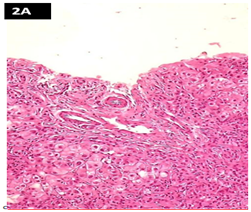

At the liver transplant unit, a second biopsy with cytokeratin 7 reveals loss of intrahepatic bile ducts, ductular proliferation with bridging fibrosis (3 out of 4), but due to the lack of regenerative nodules it does not reach the stage of cirrhosis (Figure 2A) (Figure 2B). This findings support the diagnosis of VBDS. The liver function values almost normalized but the ALP is still abnormally high.

Figure 2 (A) Portal space without bile duct (h&e).